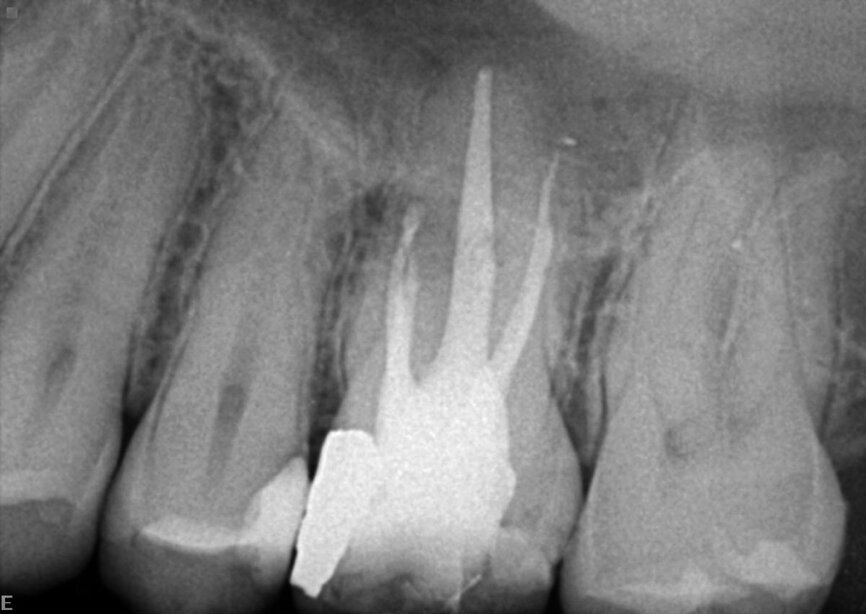

A patient was referred to the office with problems related to separated files. He was a pilot and was complaining of pus draining from his nose when flying. From the preoperative radiograph (Fig. 1), it was clear that there were two separated file fragments in the mesial canals and one cone passing beyond the apex in the palatal root. I requested an iCAT scan, and from this, the left sinus was clearly almost full with inflammatory fluid (Fig. 2) and the cone in the palatal canal was clearly emerging into the sinus. We could also see the two separated files in the two mesial canals clearly in the MPR view (Figs. 3 & 4), as well as another file entering the sinus and not attached to the canal (Fig. 5). We could see the file using different filters (Figs. 6–9), as well as the inflammation inside the sinus and the separated file. We additionally gained a better idea of the location of the cone protruding from the palatal canal into the sinus.

The treatment plan was to try to solve it with a conventional approach and if necessary to perform microsurgery to save the tooth. With the help of H-files, I managed to retrieve the cone from the palatal root, but the files inside the mesial root were impossible to bypass or even to reach with ultrasonic tips. I decided not to overdo it in order to avoid creating an additional problem, like perforating the canal, and decided to seal the canals (Fig. 10). A surgical approach was immediately taken for the mesial canals, cutting 3 mm of the mesial root using the Impact Air handpiece (SybronEndo), and this gave me a direct view of the Schneiderian membrane, where the third file was barely hanging (Figs. 11 & 12). I managed to delicate grab it and to remove it (Fig. 13). Figure 14 shows the postoperative situation, after performing retrograde preparation of the mesial canals.